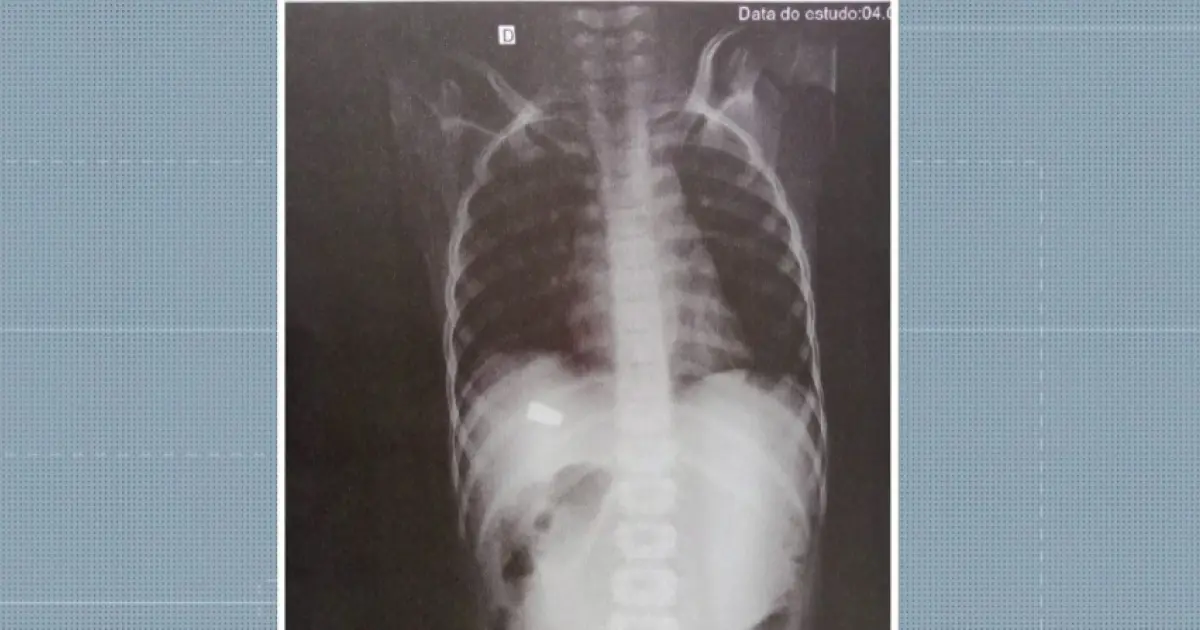

Uma imagem do raio-x do garoto mostra a região onde a vítima foi atingida pela bala. A autoria do disparo está sendo apurada pela polícia. As guias periciais foram expedidas para o entendimento do caso.